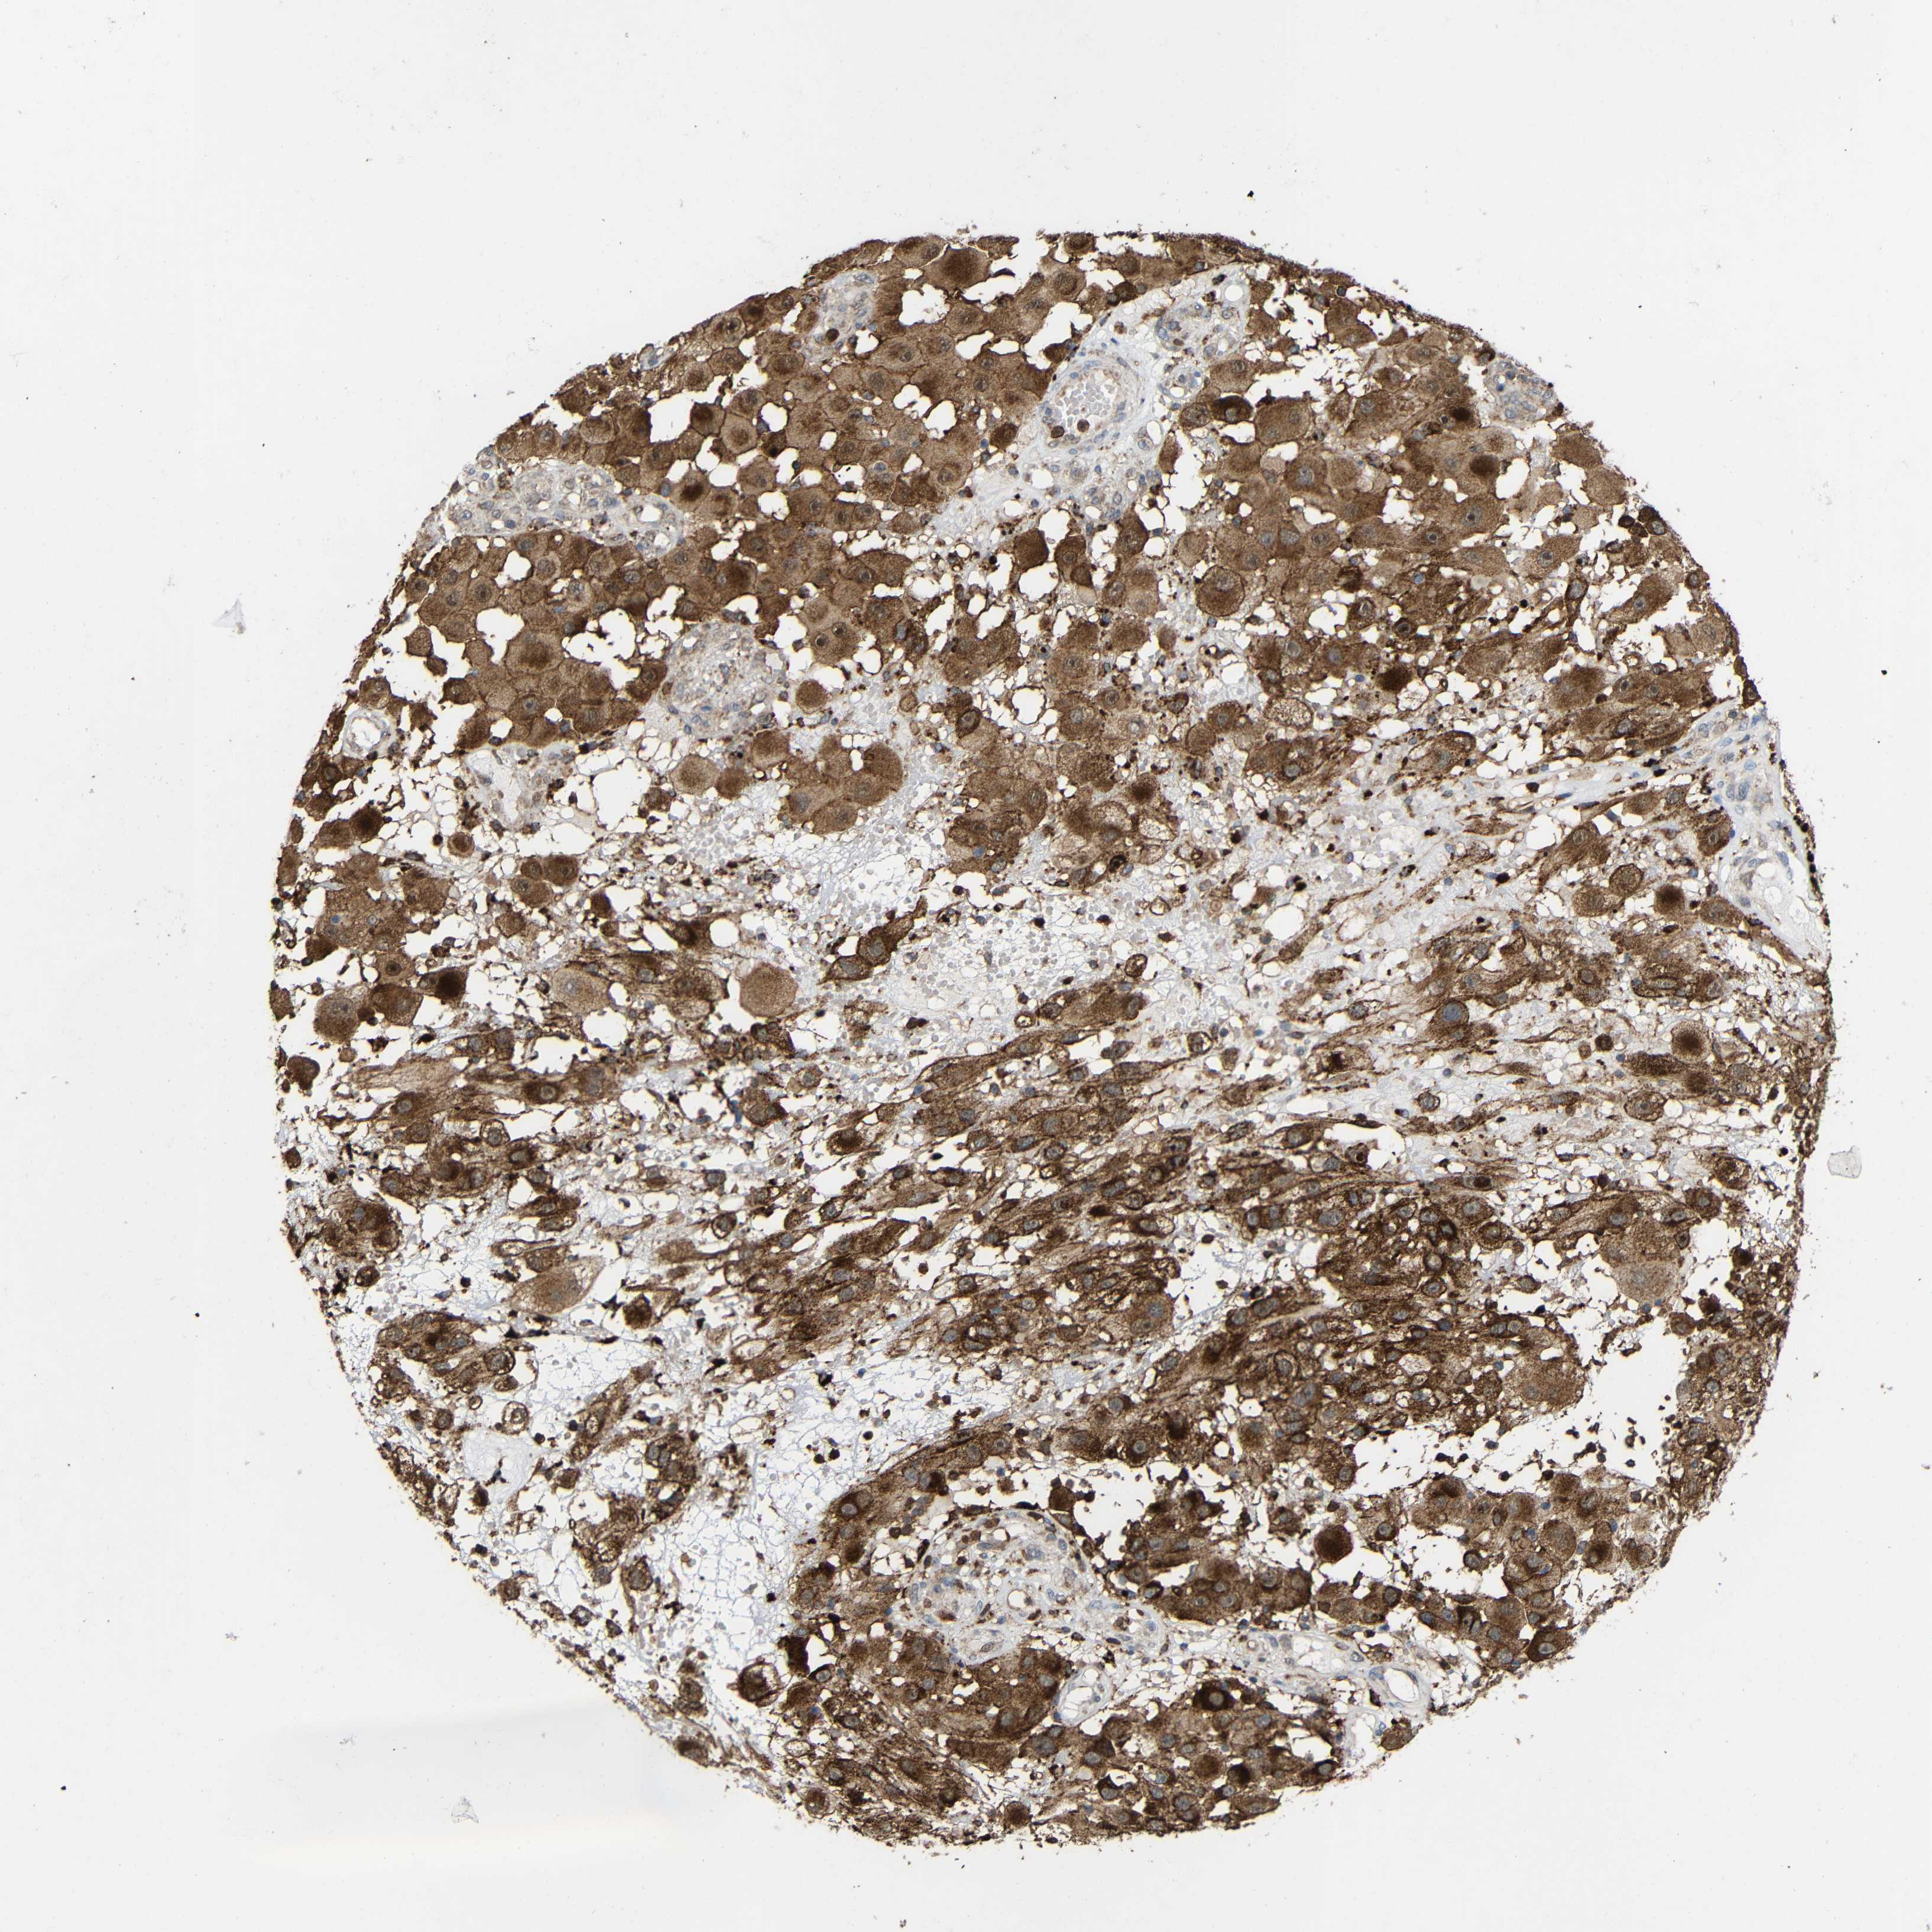

MELANOMA - Protein expressioni

A mouse-over function shows sample information and annotation data. Click on an image to view it in a full screen mode. Samples can be filtered based on level of antibody staining by selecting one or several of the following categories: high, medium, low and not detected. The assay and annotation is described here.

Note that samples used for immunohistochemistry by the Human Protein Atlas do not correspond to samples in the TCGA dataset.

Antibody stainingi

Antibody staining in the annotated cell types in the current human tissue is reported as not detected, low, medium, or high, based on conventional immunohistochemistry profiling in selected tissues. This score is based on the combination of the staining intensity and fraction of stained cells.

Each image is clickable and will lead to virtual microscopy that enables deeper exploration of all samples and also displays staining intensity scores, fraction scores and subcellular localization as well as patient and tissue information for each sample.

Antibody HPA011294

Antibody HPA012819

Staining

High

Medium

Low

Not detected

Intensity

Strong

Moderate

Weak

Negative

Quantity

>75%

75%-25%

<25%

None

Location

Nuclear

Cytoplasmic/membranous

Cytoplasmic/membranous,nuclear

Malignant melanoma, NOS

Malignant melanoma, Metastatic site